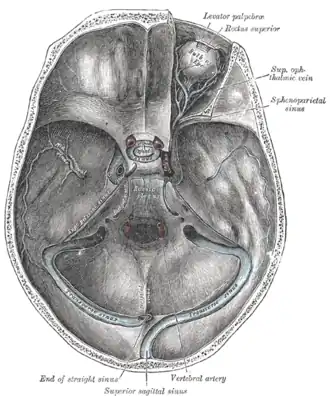

The basilar venous plexus (transverse or basilar sinus) is a venous plexus of dural venous sinuses situated upon the clivus and posterior aspect of the dorsum sellae of sphenoid bone. It interconnects the two cavernous sinuses as well as the origins of the petrous sinuses.[1]

It communicates with the anterior vertebral venous plexus.